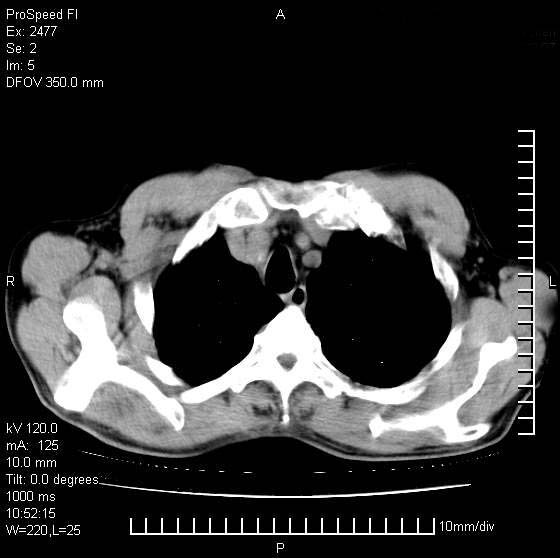

以下是引用天南地北在2007-10-9 14:29:00的发言:[br]1:右上肺结核[br]2:右肺下叶肿块:不支持肺癌,首先考虑炎性病变-肺脓疡可能性大[br]理由:1:临床病史支持,肺脓肿症状不明显应该是不规则服药造成。[br] 2:肿块边缘模糊,周围可见炎性渗出,长毛刺,内见支气管征,不过有点不规则。[br] 我感觉下肺癌这个诊断有点偏左,建议积极抗炎治疗后复查

以下是引用卜一在2007-10-9 15:55:00的发言:[br][br] [br] 1:右上肺结核[br]2:右肺下叶肿块:不支持肺癌,首先考虑炎性病变-肺脓疡可能性大[br]理由:1:临床病史支持,肺脓肿症状不明显应该是不规则服药造成。[br] 2:肿块边缘模糊,周围可见炎性渗出,长毛刺,内见空气支气管征,不过有点不规则。[br] 我感觉下肺癌这个诊断有点偏左,建议积极抗炎治疗后复查![br]支持! [br] [br] [br]

以下是引用wxy7406在2007-10-9 21:02:00的发言:[br]结合临床病史首先考虑感染性病变,但周围型肺癌不能除外,1.患者年龄偏大2.临床有咯血3.(也觉得是最重要的一点)病灶内有偏心性空洞。

以下是引用王仕学在2007-10-9 13:48:00的发言:[br]右下肺周围性肺癌可能性大,最好活检吧

以下是引用hhcckk在2007-10-9 15:18:00的发言:[br]右上肺病灶考虑结核,病灶多种形态并存(纤维化、增殖性病灶并存)[br]右下肺病灶比较难说,个人意见更趋向于“天南地北”的诊断----肺脓肿[br]1、病人有明显的寒战,高热,肿瘤病人很少出现[br]2、病灶周围的肺纹理走向柔和,没有肿瘤病灶常见的集束征[br]3、病灶边缘的毛刺较长,恶性肿瘤多为短毛刺[br]痰中血丝和病人的年龄是两个不利于良性肿块的因素,建议早点活检

以下是引用ydx_74在2007-10-9 15:53:00的发言:[br]右上肺结核,右下中心性肺癌可能大,肺门淋巴结肿大。